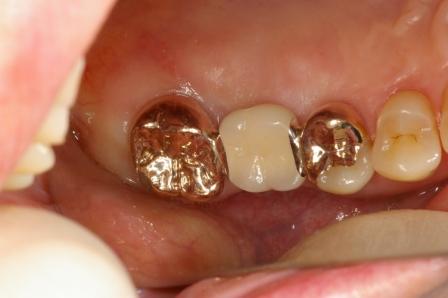

続いて奥歯のブリッジの症例です。

奥歯の2本を土台にしてブリッジを入れました。歯のないところにはブリッジを入れる治療が現在までの主流でした。